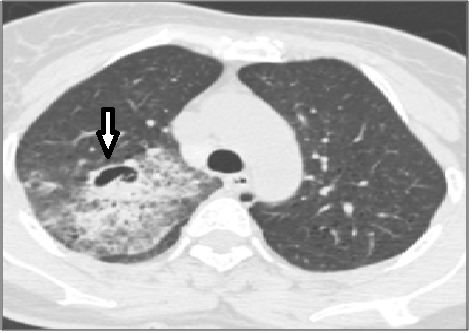

图1:腐生性曲霉菌。肺窗的仰卧MDCT扫描显示重力依赖性腔内肿块。